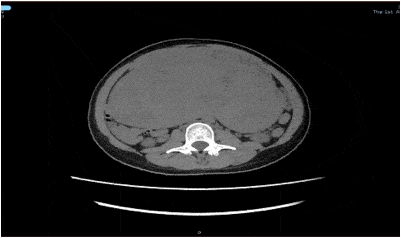

术前彩超检查 子宫后方巨大肿物

“未见其人 , 先见其腹”!体重50公斤的黄女士来暨南大学附属第一医院就诊时 , 她的肚子却巨大得异常突兀 , 经过全腹CT检查 , 结果显示:腹盆腔内见一巨大软组织肿块影 , 大小约22cm*10cm*28cm 。 子宫后发盆腹腔探及一实性光团 , 考虑盆腹腔巨大实性占位病变 。 抽血检查显示 , 包括肿瘤标记物均正常 。